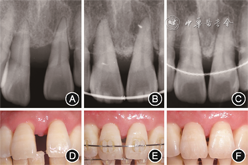

像(4)下前牙牙周手术治疗:在正畸排齐压低下前牙后,于正畸治疗后17个月行牙周植骨术联合GTR,翻瓣后可见31、32间存在4 mm骨内缺损,刮净肉芽组织后植入骨粉(Bio-Oss,Geistlich,瑞士),并覆盖可吸收胶原膜(Bio-Gide,Geistlich,瑞士),缝合(图9)。结合术前根尖片及术中口内像可见正畸压入后,31、32间牙槽骨吸收类型由水平型吸收转为垂直型吸收,有利于牙周再生术的成功实施,术后根尖片进一步显示骨充填良好(图10)。

对牙槽骨呈垂直型吸收的患牙,正畸治疗前实施牙周再生性手术可创造有利条件,如在正畸压低前行GTR有助于新骨形成和临床附着增加[5],但牙周再生性手术后多久开始正畸治疗目前尚无定论。Roccuzzo等[6]在牙周再生性手术后8~12个月施加正畸力,并指出在组织完全愈合即术后至少6个月进行正畸移动,可获得稳定的再生效果。也有学者认为术后早期可开始正畸治疗:有动物实验表明牙周再生性手术后1个月应用正畸力可获得牙周组织的良好再生[7];多篇病例报道同样支持术后宜早期进行正畸治疗[8, 9, 10]。本病例上前牙GTR术中加入Bio-Oss,术后10周开始正畸治疗。牙周再生性手术前11、21平均PD为4.25 mm,正畸治疗结束9个月平均PD为2.25 mm,与术前相比平均附着获得为3.08 mm,术后根尖片显示骨充填良好,可为垂直型骨吸收患牙牙周再生性手术后正畸治疗时机的选择提供参考。

本例患者下前牙牙槽骨呈水平型吸收,由于水平型骨吸收区域无法创造充足且稳定的再生空间,通常认为此类骨缺损并非牙周再生性手术的最佳适应证[11]。动物研究显示,正畸治疗可改善大鼠牙髓、牙周膜及牙槽骨中的血液循环[12]。正畸压低还可将患牙牙槽骨缺损类型由水平型吸收转变为垂直型吸收,Cao等[13]对56颗存在水平型骨缺损的伸长前牙采用正畸压低联合牙槽嵴上纤维环切术治疗,有14颗患牙骨缺损类型转变为垂直型吸收。本病例通过正畸治疗排齐牙列并压低下前牙,成功形成4 mm的骨内缺损,创造了足够的再生空间,随后进行牙周再生性手术并取得良好效果,为牙槽骨水平型吸收患牙的牙周再生治疗提供了参考。

3.牙周再生性手术联合正畸压低治疗也是恢复前牙美学的有效手段:牙龈乳头缺陷导致的“黑三角”是影响前牙美学的重要问题,“黑三角”的形成与牙槽嵴顶至相邻牙接触点的距离、相邻牙根间分离角等有关[14]。重度牙周炎常伴有牙槽骨缺损及牙齿病理性移位,联合应用增加骨嵴顶高度的牙周手术及关闭间隙并改变相邻牙根间分离角的正畸移动是解决此类患者前牙美学问题的有效手段[15, 16]。本例患者上前牙扇形移位,11、21间存在约4 mm间隙,牙周基础治疗后仍有较深的牙周袋,牙槽骨呈垂直型吸收。正畸医师联合会诊后制订的治疗策略如下:首先采用牙周再生性手术增加牙槽骨垂直向高度,随后正畸压低内收上前牙并联合邻面去釉调整邻牙接触区,尽量控制11、21间牙槽嵴顶至相邻牙接触点距离在5 mm以内,以避免上前牙的美学缺陷。治疗后上前牙牙间隙关闭,11、21间龈乳头形态良好,患者对治疗效果满意。